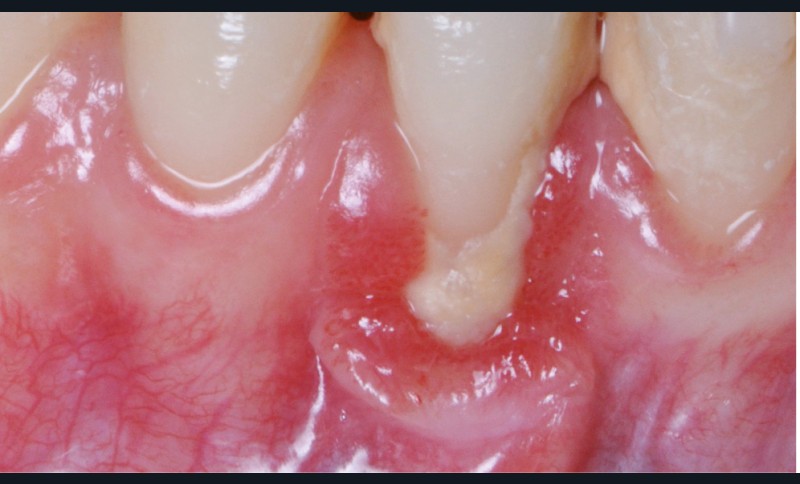

Zuchelli et coll. [1] définissent quatre causes à l’origine des récessions gingivales à la suite d’une déhiscence osseuse : les causes traumatiques (fig. 1) par le brossage, le surcontour prothétique, les piercings ; les causes bactériennes (fig. 2) liées à une inflammation marginale ; les causes virales par le virus de l’herpès simple ; et les origines mixtes, à savoir traumatiques et bactériennes (fig. 3). Le diagnostic de récession liée à la plaque dentaire dépend de la présence de dépôts tartriques et/ou d’inflammation des tissus environnant les zones exposées. En présence d’une origine mixte, la récession est d’abord initiée par un brossage traumatisant, rendant la surface radiculaire hypersensible ou irrégulière, ayant une répercussion négative sur le brossage et l’accessibilité à l’hygiène.